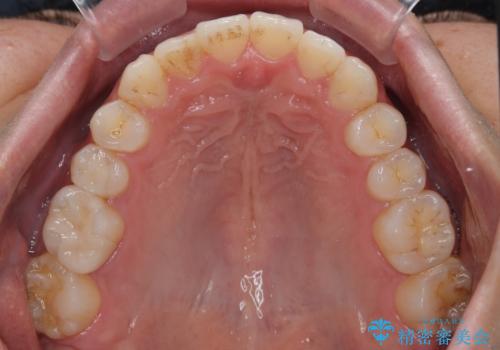

前歯のデコボコと突出感をマウスピース矯正できれいに

- 上下前歯のデコボコと突出感を気にして来院された患者様です。

目立たない装置を希望されたため、インビザラインによるマウスピース矯正を行うこととしました。

矯正治療後に銀歯をセラミックに替えたいとの要望があり、概ね歯列が整ったところで銀歯をセラミックに替え、仕上げにインビザライン1セットを使用して最終的に歯列を整えました。